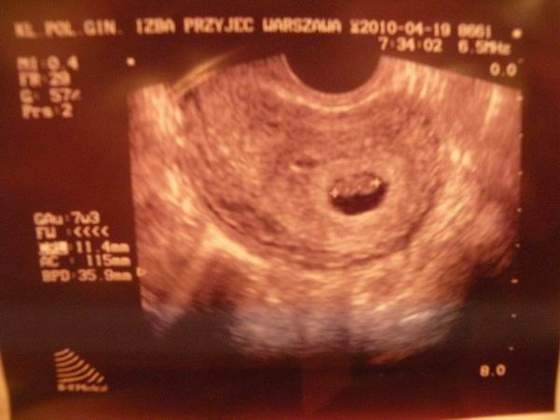

u mnie kropki nie były tak symetryczne, ale kojarzy mi się, że jedno to zarodek a drugie to kosmówkaola ja tam widze dwie kropki :-O jeszcze sie okaze ze to blizniakii bedzie julek i julia :-)